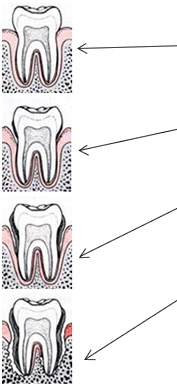

Razvoj parodontne bolesti

Zdrave desni - čvrste desni, zdrave blijedoružičaste boje, nema krvarenja.

Gingivitis - upalno promjenjene desni, intenzivno crvene boje, krvarenje kod četkanja, a ponekad i spontano. Prisutan otok gingive što dovodi do formiranja plitkih pseudodžepova koji pospješuju zadržavanje naslaga.

Umjereni parodontis - kronična upalna destrukcija potpornog tkiva zuba, džepovi postaju 4-6 mm duboki, javlja se slab zadah.

Uznapredovali paradontitis - ireparabilno oštećenje potpornog tkiva i okolne kosti, džepovi su duboki preko 6 mm i krvare, hranjenje je otežano, slab zadah je konstantan, loše opće stanje, vjerojatan gubitak zuba.